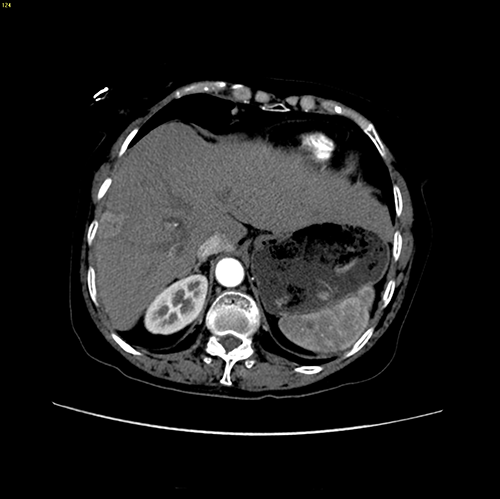

右肝肝癌---右肝肿瘤切除